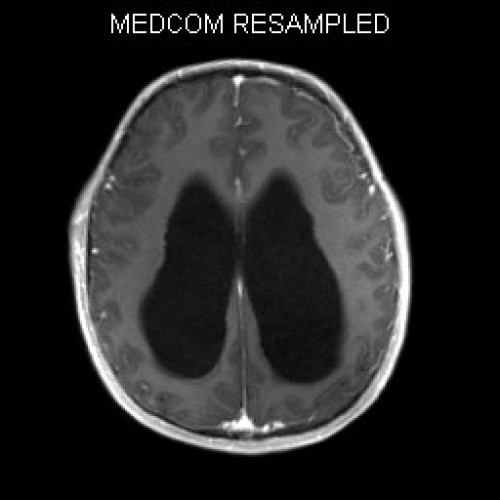

ICD: C75.3

ICD: G91.9

12-jähriger Junge. Die Eltern werden zu einem Gespräch bei der Klassenlehrerin gebeten, weil ihr Sohn sehr unaufmerksam geworden sei und seine Leistungen in der Schule bedenklich abgenommen hätten. Er droht das Klassenziel der 6. Klasse nicht zu erreichen.

Den Eltern war seit längerer Zeit bereits aufgefallen, dass sich ihr Sohn nach der Schule am liebsten ins Bett lege, um für eine Stunde einen Mittagsschlaf zu halten.